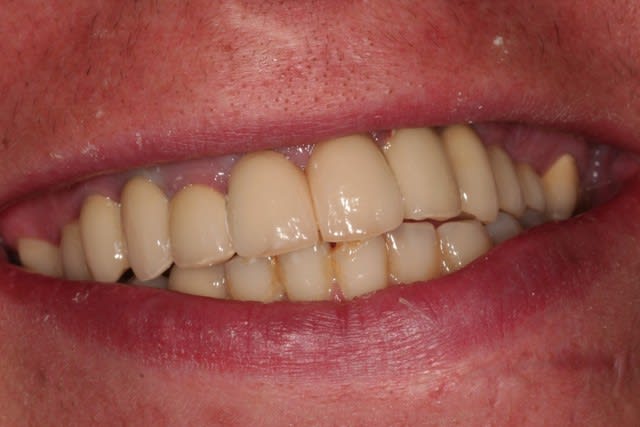

Sourire déf poaydl - Eugenol

alhoun

11/07/2007 à 21h13

pardonnez les quelques excès de ciment!!

Une question de novice,est ce parce que les couronnes de 15,24 et 25 sont sur implants qu'elles sont plus "rentrées" que les autres? impossible de récupérer le bombé de l'arcade comme avec des ceramiques sur couronnes?

je te jure alhoun, ce n'est pas une critique (beau travail) mais une information pour une non "implanteuse" (tiste?)

non, les prémols sont dans leur position d'origine, c'est le genre de sourire qu'avait le patient...nous avons repositionné les canines par rapport à d'anciennes photos, et je crois que c'est ça qui donne cet effet.

là ou j'ai ce genre de problème, par contre, c'est en 36 et 37. malgré des extractions complètement atraumatiques, si ce mot peut être employé sur ce cas précis, il y a eu perte osseuse, et je suis légèrement lingualé.